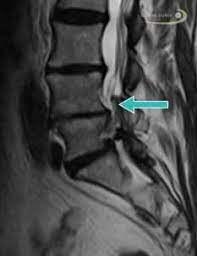

Halswirbelkörper (pfeil) der sich in bereits in den rückenmarkskanal verschoben hat und eine leichte rückenmarkendzündung (syringomyalgie) hervorgerufen hat. Die mrt ist die untersuchungsmethode der ersten wahl zur abklärung einer erkrankung an der halswirbelsäule. Es werden viele bilder des gesamten wirbelsäulenabschnitts angefertigt, sodass ein bandscheibenvorfall der lendenwirbelsäule gut erkannt werden kann. Verdacht auf bursitis hat sich nicht bestätigt, das mrt hüften waren o.b. Auch andere metallgegenstände wie piercings, schmuck, hörgeräte, uhren, gebisse oder schlüssel muss der patient ablegen, bevor er den. Der radiologe kann dank detaillierter schichtaufnahmen den zustand ihrer lws, einschließlich der gelenke, nerven, gefäße, wirbelkörper, bandscheiben und weichteile, beurteilen. Der arzt nennt diese verschiedenen aufnahmetechniken wichtungen. Noch länger muss auf die ergebnisse der forschung warten. Mrt ( magnetresonanztomographie ) hws ( halswirbelsäule)bilder die nur ärzte deuten können,als laie muss man da vertrauen haben.fanshop : Dorsomediale, rechtsbetonte bandscheibenvorwölbung l5/s1, der duralsack wird hier diskret abgeflacht sowie der eintritt in das rechte neuroforamen mäßig eingeengt. Mrt bilder kniegelenk sind musik in den ohren. Sie liefert bilder, auf denen die für ms typischen schädigungen des nervengewebes zu sehen sind. Lws ist frei, die schmerzen beginnen auch erst unter dem gesäß.

Aber entzündungen oder tumoren des knochens können mit der mrt dargestellt werden: Die mrt ist die untersuchungsmethode der ersten wahl zur abklärung einer erkrankung an der halswirbelsäule. Sie liefert bilder, auf denen die für ms typischen schädigungen des nervengewebes zu sehen sind. Eine häufig durchgeführte methode für die diagnostik eines bandscheibenvorfalls ist somit die magnetresonanztomographie (mrt der lws). Für mich sehen die bilder nicht sehr dramatisch aus aber ich hab ja auch keine ahnung. Manchmal können derartige radiologisch nachweisbare veränderungen aber auch fehlen. Mrt der lws t2 (linkes bild) weiß kann man die entzündung der lendenwirbelsäule erkennen, da die bandscheibe durch die fehlstellung aufgebraucht wurde und nun knochen auf knochen reibt und eine entzündung des knochens entsteht. Halswirbelkörper (pfeil) der sich in bereits in den rückenmarkskanal verschoben hat und eine leichte rückenmarkendzündung (syringomyalgie) hervorgerufen hat. Mrt der halswirbelsäule in sagitaler projektion. Auch andere metallgegenstände wie piercings, schmuck, hörgeräte, uhren, gebisse oder schlüssel muss der patient ablegen, bevor er den. Mrt der lws t2 (linkes bild) weiß kann man die entzündung der lendenwirbelsäule erkennen, da die bandscheibe durch die fehlstellung aufgebraucht wurde und nun knochen auf knochen reibt und eine entzündung des knochens entsteht. Die entzündung greift hierbei sekundär auf die bandscheibe über. Allerdings haben sie eine venenverengung.